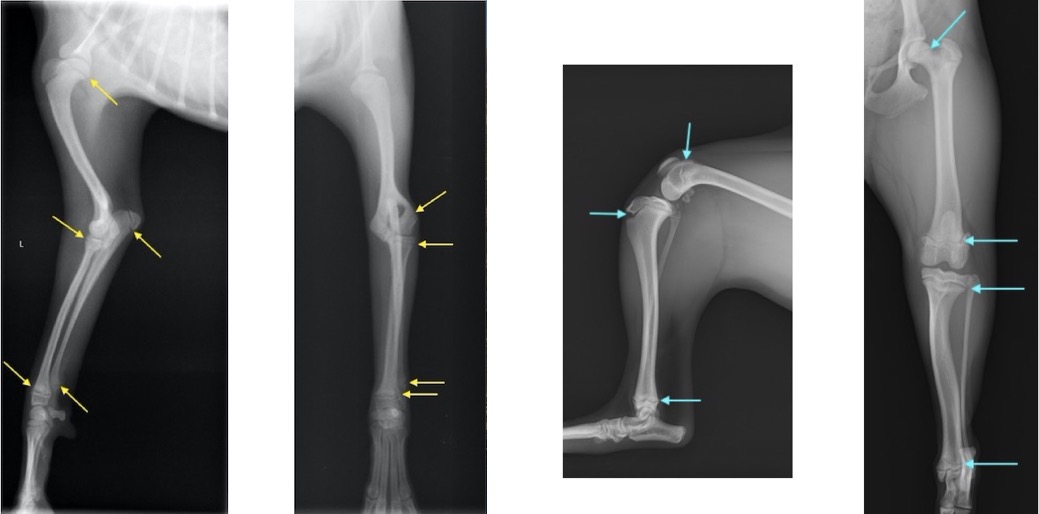

単純X線検査における四肢の成長板(矢印が成長板です)